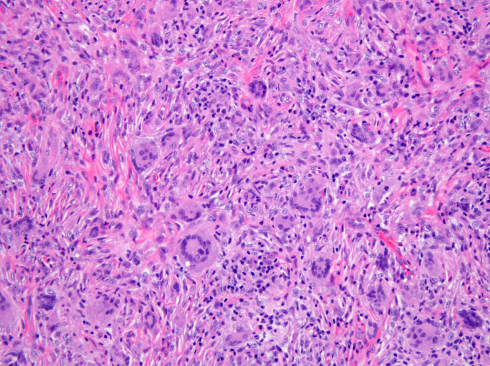

The pathogenesis of JXG is thought to be of reactive origin, namely local tissue injury that evoked a histioxanthomatous reaction.[13] Histologically, the cutaneous infiltrate includes a mixture of foamy histiocytes, lymphocytes, fibroblasts and multinucleated giant cells, including Touton-type giant cells, with a moderate amount of collagen deposition (Figures 4-5). A Touton giant cell is a multinucleated cell that contains a wreath of nuclei surrounding homogeneous cytoplasm, with a rim of foamy cytoplasm peripheral to the nuclei. Other inflammatory cells may be present to varying degrees.[16] JXG cells stain positive for CD68, have variable reactivity for factor XIIIa and stain negative for CD1a, S100, CD20716. JXG does not carry BRAF V600E mutation, except in patients with both Langerhans’ cells histiocytosis (LCH) and JXG (non-Langerhans' cells histiocytosis) diseases and in the aggressive forms of JXG.[8] Development of JXG after chemotherapy for LCH has been reported in 11 patients.[16] One theory proposed the coexistence of LCH and JXG could be the result of chemotherapy-induced maturation of Langerhans’ cells into macrophages, in particular foamy cells.[17] Another theory hypothesized that JXG may be triggered by LCH lesions through the production of a cytokine storm.[9][16]

The classic histopathologic findings include multinucleated Touton giant cells in addition to epitheloid histiocytes, lymphocytes and eosinophils (Figures 4-5). However, Touton giant cells are not mandatory for the diagnosis of JXG. In early JXG, small- to intermediate-sized mononuclear histiocytes display a compact sheet-like infiltrate; the lipidization of histiocytes is not detectable and Touton giant cells are rarely found. The pale eosinophilic cytoplasm is sparse to moderate and does often not contain any lipid vacuoles or only fine vacuoles.[24]